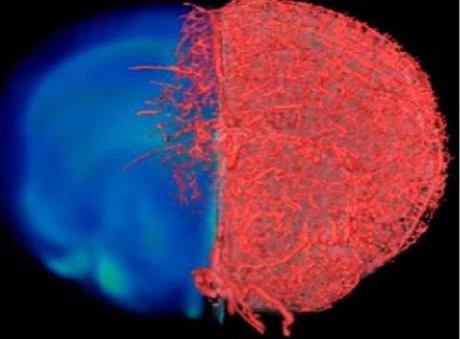

Les chercheurs de Baltimore ont développé et testé une nouvelle approche d'imagerie qui va permettre aux scientifiques de capturer des images de vaisseaux sanguins à différentes échelles spatiales : VascuViz est basé sur un mélange de polymères à prise rapide qui remplir les vaisseaux sanguins et les rend visibles -avec de multiples techniques d'imagerie. Le composé, testé in vitro, puis dans une variété de tissus de souris, par perfusion à travers le système vasculaire de modèles de cancer du sein, dans les muscles des jambes, le cerveau ou encore les tissus rénaux a permis, via l'IRM, la tomodensitométrie et la microscopie optique d’obtenir des visualisations 3D du système vasculaire.

L'approche permet plus globalement aux chercheurs de visualiser avec une grande précision la structure du système vasculaire d'un tissu. Ces données, en conjonction avec un modèle d’intelligence artificielle, des images complémentaires, d’autres biopsies tissulaires, permettent de clarifier le rôle complexe du flux sanguin dans la maladie. Ces images à l’échelle du vaisseau sanguin vont permettre de mieux cerner la biologie des maladies caractérisées par des anomalies du flux sanguin mais également décrypter les structures et les fonctions des différents tissus du corps.

VascuViz surmonte ce problème en rendant la structure des plus grandes artères au micro-vaisseau le plus minuscule visible avec tout un panel de techniques d'imagerie classiques, ce qui permet aux chercheurs d’accéder à une compréhension spatiale de la structure et de la santé des vaisseaux, ainsi que des tissus environnants. VascuViz permet d’estimer plus précisément des caractéristiques telles que le flux sanguin dans les vaisseaux sanguins réels, puis de combiner ces données avec des informations complémentaires, telles que la densité cellulaire. Ainsi, des données obtenues grâce à VascuViz sont ensuite entrées dans des modèles informatiques du flux sanguin,

tels que les modèles développés pour les cancers, ce qui offre une image précise de l’évolution de la maladie.